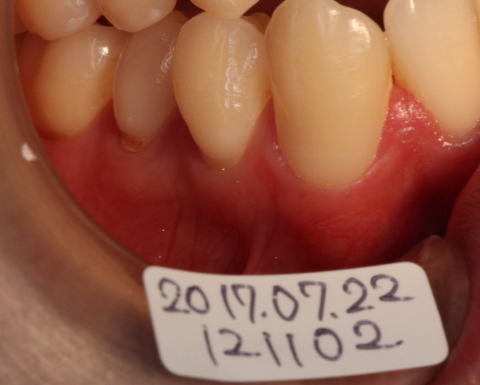

2017-07-22 44,45の状態。歯ぐきの退縮により象牙質の露出。 46番は良好 |